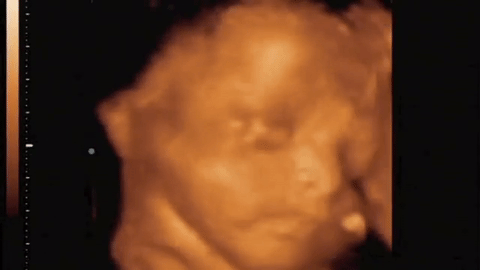

S ONE STRANE VEROVATNOG

DOKTORI U ŠOKU: 10 dana nakon pobačaja čuli su otkucaje srca u stomaku!? (VIDEO)